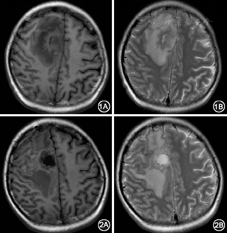

入院时体格检查发现左侧腱反射稍亢进,左侧肢体肌力0级。外周血白细胞9.93×109/L,中性0.87,淋巴0.10,血红蛋白73 g/L。头颅MRI提示右侧额叶大脑镰旁团块样异常信号约3.0 cm×4.1 cm,灶周大片水肿信号,花环样增强。灶周及右侧颞叶皮层下见数个环形增强小病灶(图1),考虑脑脓肿可能。PET-CT检查和化疗前相比,颅内为新出现病灶。

入院后于2012年9月13日全麻下行颅内占位探查活检术,术中可见灰白色脓性物质,内含大量黄色脓液,术中冰冻及术后病理提示颅内变性、坏死物及脓细胞,符合脑脓肿。术后给予静脉使用万古霉素、美罗培南及口服复方新诺明治疗,体温可降至正常,肌力无好转。7 d后脓肿脓液培养回报为单核细胞增生李斯特菌,药敏显示对青霉素G、复方新诺明及氨苄西林均敏感,故将万古霉素调整为静脉青霉素4 MU,每4小时1次,余治疗同前。患者左侧肌力逐渐恢复至3级,复查头颅MRI显示病灶缩小,周围水肿消退(图2)。但患者高热不退,腰穿脑脊液压力、常规及生化均正常,血培养阴性。2周后因肺部感染及反复菌血症,出现感染性休克、导管相关性血流感染,血培养示铜绿假单胞菌及热带念珠菌感染,于2012年11月11日病情加重,抢救无效死亡。